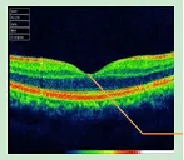

宿艳副主任说,曾经有一位50岁的女性患者老年性黄斑变性引起黄斑水肿,当时患者诉说右眼看东西模糊,视物变形变小,眼前常有黑影浮现。多次抗VEGF治疗后,病情反复。发病10个月时来就诊,经中药、针刺治疗,期间抗VEGF治疗1次,半年后眼底好转。光学相干断层扫描(OCT)检查发现眼底还有出血,黄斑中心凹处高起水肿。经过3个多月的中药治疗,患者病情大有好转,水肿明显减轻,OCT检查可见黄斑水肿减轻。半年后水肿大部分消失,视力提高到0.4到0.6。

治疗前,眼底见出血和水肿

中西医结合治疗半年后,结构基本正常纯中药治疗黄斑囊样水肿效果虽好,却有一定的局限性,除非是依从性好的患者,否则很容易半途而废。如果辨证不得法,疗效也会受影响。而单独用抗VEGF药物治疗,容易使病情拖延,影响视功能的恢复。一方面用抗VEGF药物迅速减少眼内VEGF的浓度,另一方面中医中药辨证治疗,降低血液粘稠度,抑制水肿,改善微循环和视网膜内外屏障,降低微血管病变的可能性。两者优势互补,标本兼治,既可以减少抗VEGF药物的使用次数,又能降低治疗的成本。